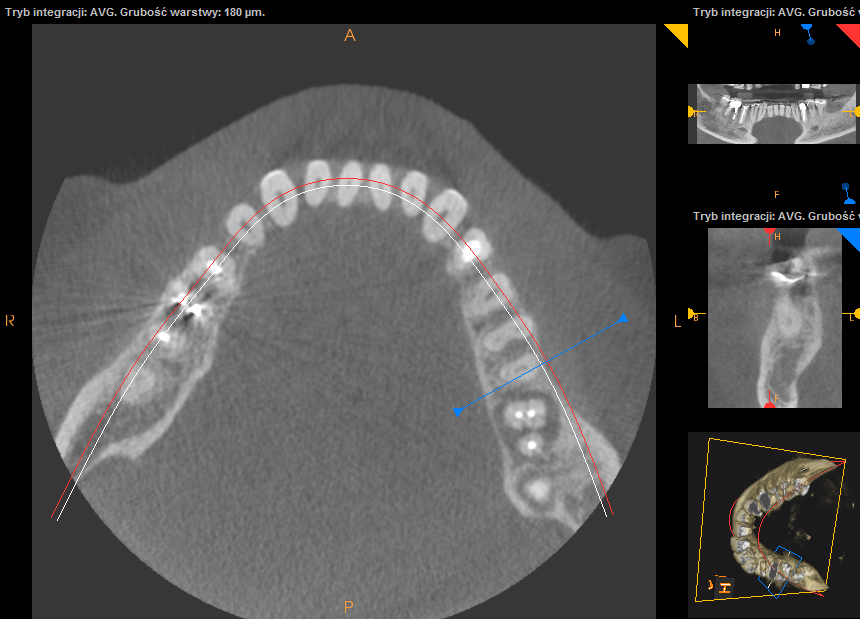

Ten problem najczęściej dotyczy zębów trzonowych żuchwy oraz górnych przedtrzonowców. Może również towarzyszyć wadom zgryzu, w zębach zniszczonych przez erozję, abrazję lub atrycję. Pionowe złamanie korzenia jest trudne do zdiagnozowania. Zdjęcia RTG nie zawsze bowiem ukaże „całą prawdę”. Coraz powszechniej używane obrazowanie CBCT (3D) pomaga w postawieniu diagnozy pionowego złamania zęba lub korzenia.

Do pionowego złamania korzenia zęba może dojść podczas zabiegu leczenia kanałowego poprzez używanie zbyt dużej siły w czasie wypełniania lub oczyszczania kanału. Może być również spowodowane zaklinowaniem się narzędzia w kanale. Pionowe korzenia zęba zawsze prowadzi do usunięcia całego zęba. Dbałość o profilaktykę i terminowe zgłaszania się do gabinetu stomatologicznego z towarzyszącą diagnostyką rentgenowską znaczącą redukuje te ryzyka.